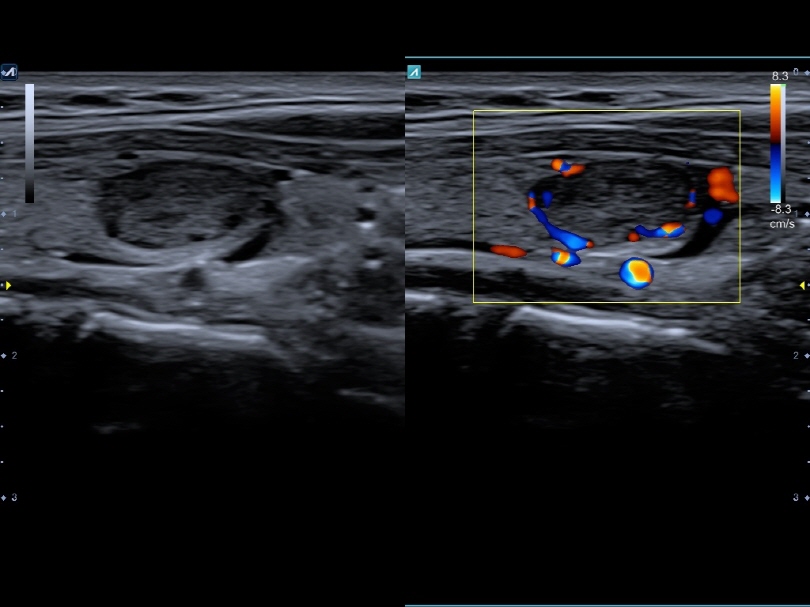

L8-17H

High density linear transducer(8-17MHz)

Application:

Breast, EM, MSK, Vascular, Small Parts

L3-12H

High density linear transducer (3-12MHz)

Application:

Breast, EM, MSK, Vascular, Small Parts

L3-12HWD

High density wide footprint linear transducer (3-12MHz)

Application:

Breast, EM, MSK, Vascular, Small Parts, Appendix

L3-12T

Linear transducer (3-12MHz)

Application:

Breast, EM, MSK, Vascular, Small Parts, Appendix